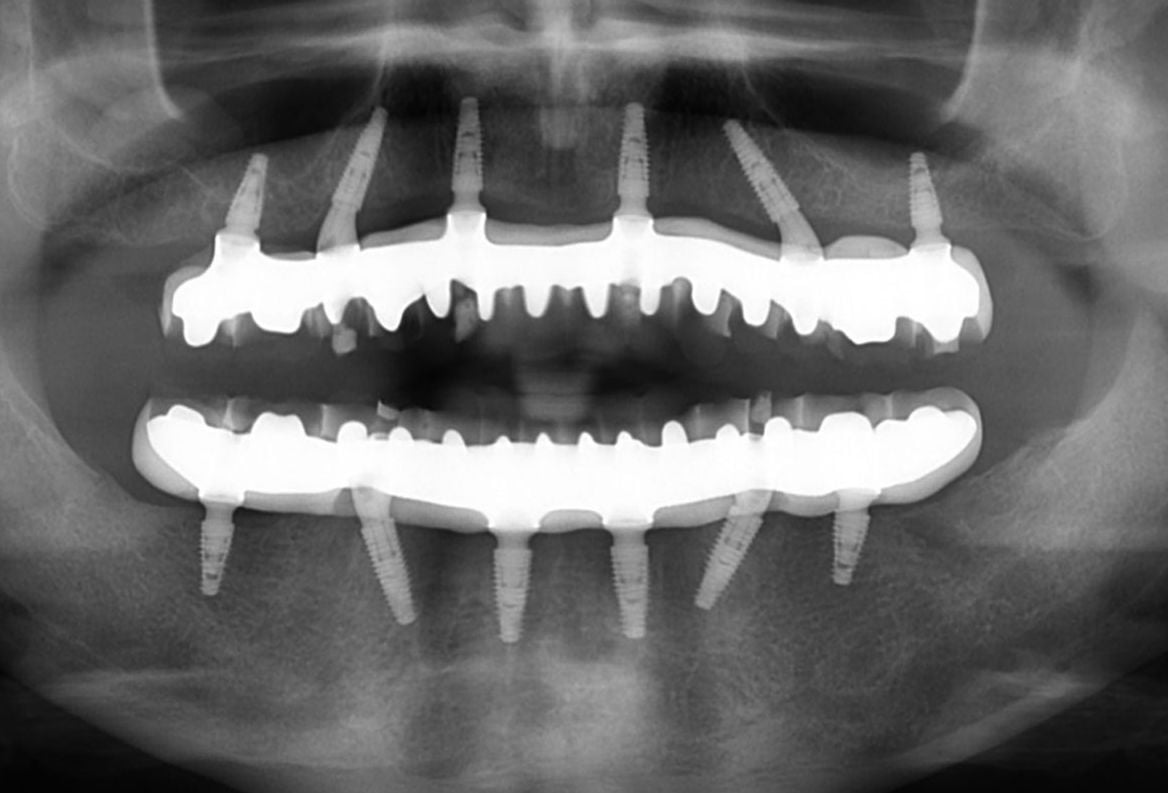

He met with myself, and we went through the treatment in detail with him. CT scans were carried out in the planning phase and each step was explained to him in detail.

The procedure took a few months from start to finish to fully complete, but when it was done, Mike was amazed at the result. He was also very reassured every step of the way by myself and all staff members at the clinic.

The implant retained false teeth looked and felt like real teeth, and Mike could chew and speak without any difficulty. The new teeth were also easy to clean and maintain, which was a huge relief for him.